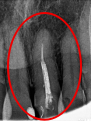

女性 Sさん 50代 (オールセラミック冠)

主訴

左上の差し歯がとれたままになっている。

治療内容

レントゲンを撮り詳しく診てみると、歯根が破折して保存することができず、抜歯する必要があることがわかりました。抜歯後、オールセラミックブリッジで補綴(欠損した部分を人工物で補う)しました。ブリッジの支台になっている後方の歯は、根尖性歯周炎(根の先端で問題を起こしている)でしたので、根管治療をしています。

所感

抜歯後、欠損部分を補う方法には、1本だけの部分入れ歯、ブリッジ、インプラントの3つの方法があります。この患者さんは、ブリッジを選択されました。メタルフリーの治療を希望されましたので、土台をファイバーコアにし、オールセラミックのブリッジをかぶせました。患者さんは、お口の中の金属を徐々に減らしていきたいということです。体全体の健康のことを考えると正しいことです。

オールセラミック冠(失活歯)1本:¥104,500(税込)

オールセラミック冠(生活歯)1本:¥93,500(税込)

ポンティック1本:¥93,500(税込)

合計:¥291,500(税込)

Before

After